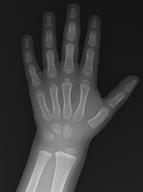

An X-ray showing the lower arm, wrist, and hand.

Las radiografías son imágenes del interior del cuerpo. Un equipo de rayos X produce estas imágenes mediante el uso de ondas de energía que se conocen como radiación. Los huesos y los tejidos del cuerpo absorben distintas cantidades de radiación, que se muestran en las radiografías en tonos de negro, gris y blanco.

Las radiografías pueden usarse para detectar muchos problemas de salud. Los médicos pueden usarlos para detectar problemas como fracturas de huesos, problemas pulmonares y algunos tipos de cáncer.